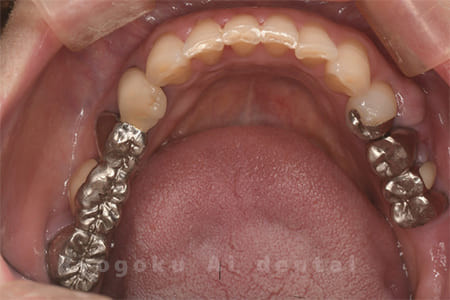

- 原因

- 右下5・6番歯根破折

- 治療内容

- ノンクラスプデンチャー

右下の歯が割れているとのことでご来院された患者様です。全身疾患も考慮し、目立たない入れ歯を相談して決定し、大変満足いただけました。